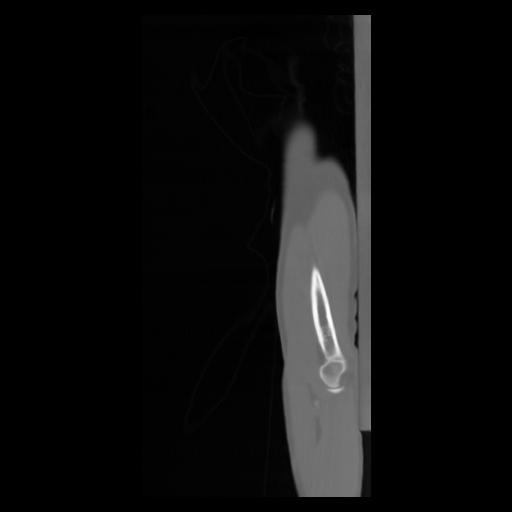

30 CUERPO,CE,Sagittal,3.000,CUERPO,Sagittal,